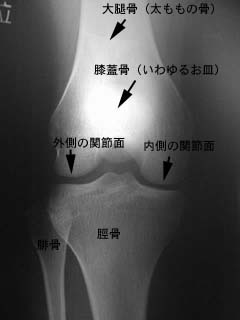

膝のレントゲン写真

右膝の関節の正面から見たレントゲン写真です。

内側や外側の関節面はレントゲンでは透き間が空いているように写ります。この間には軟骨がありますが、軟骨はレントゲンには写りません。